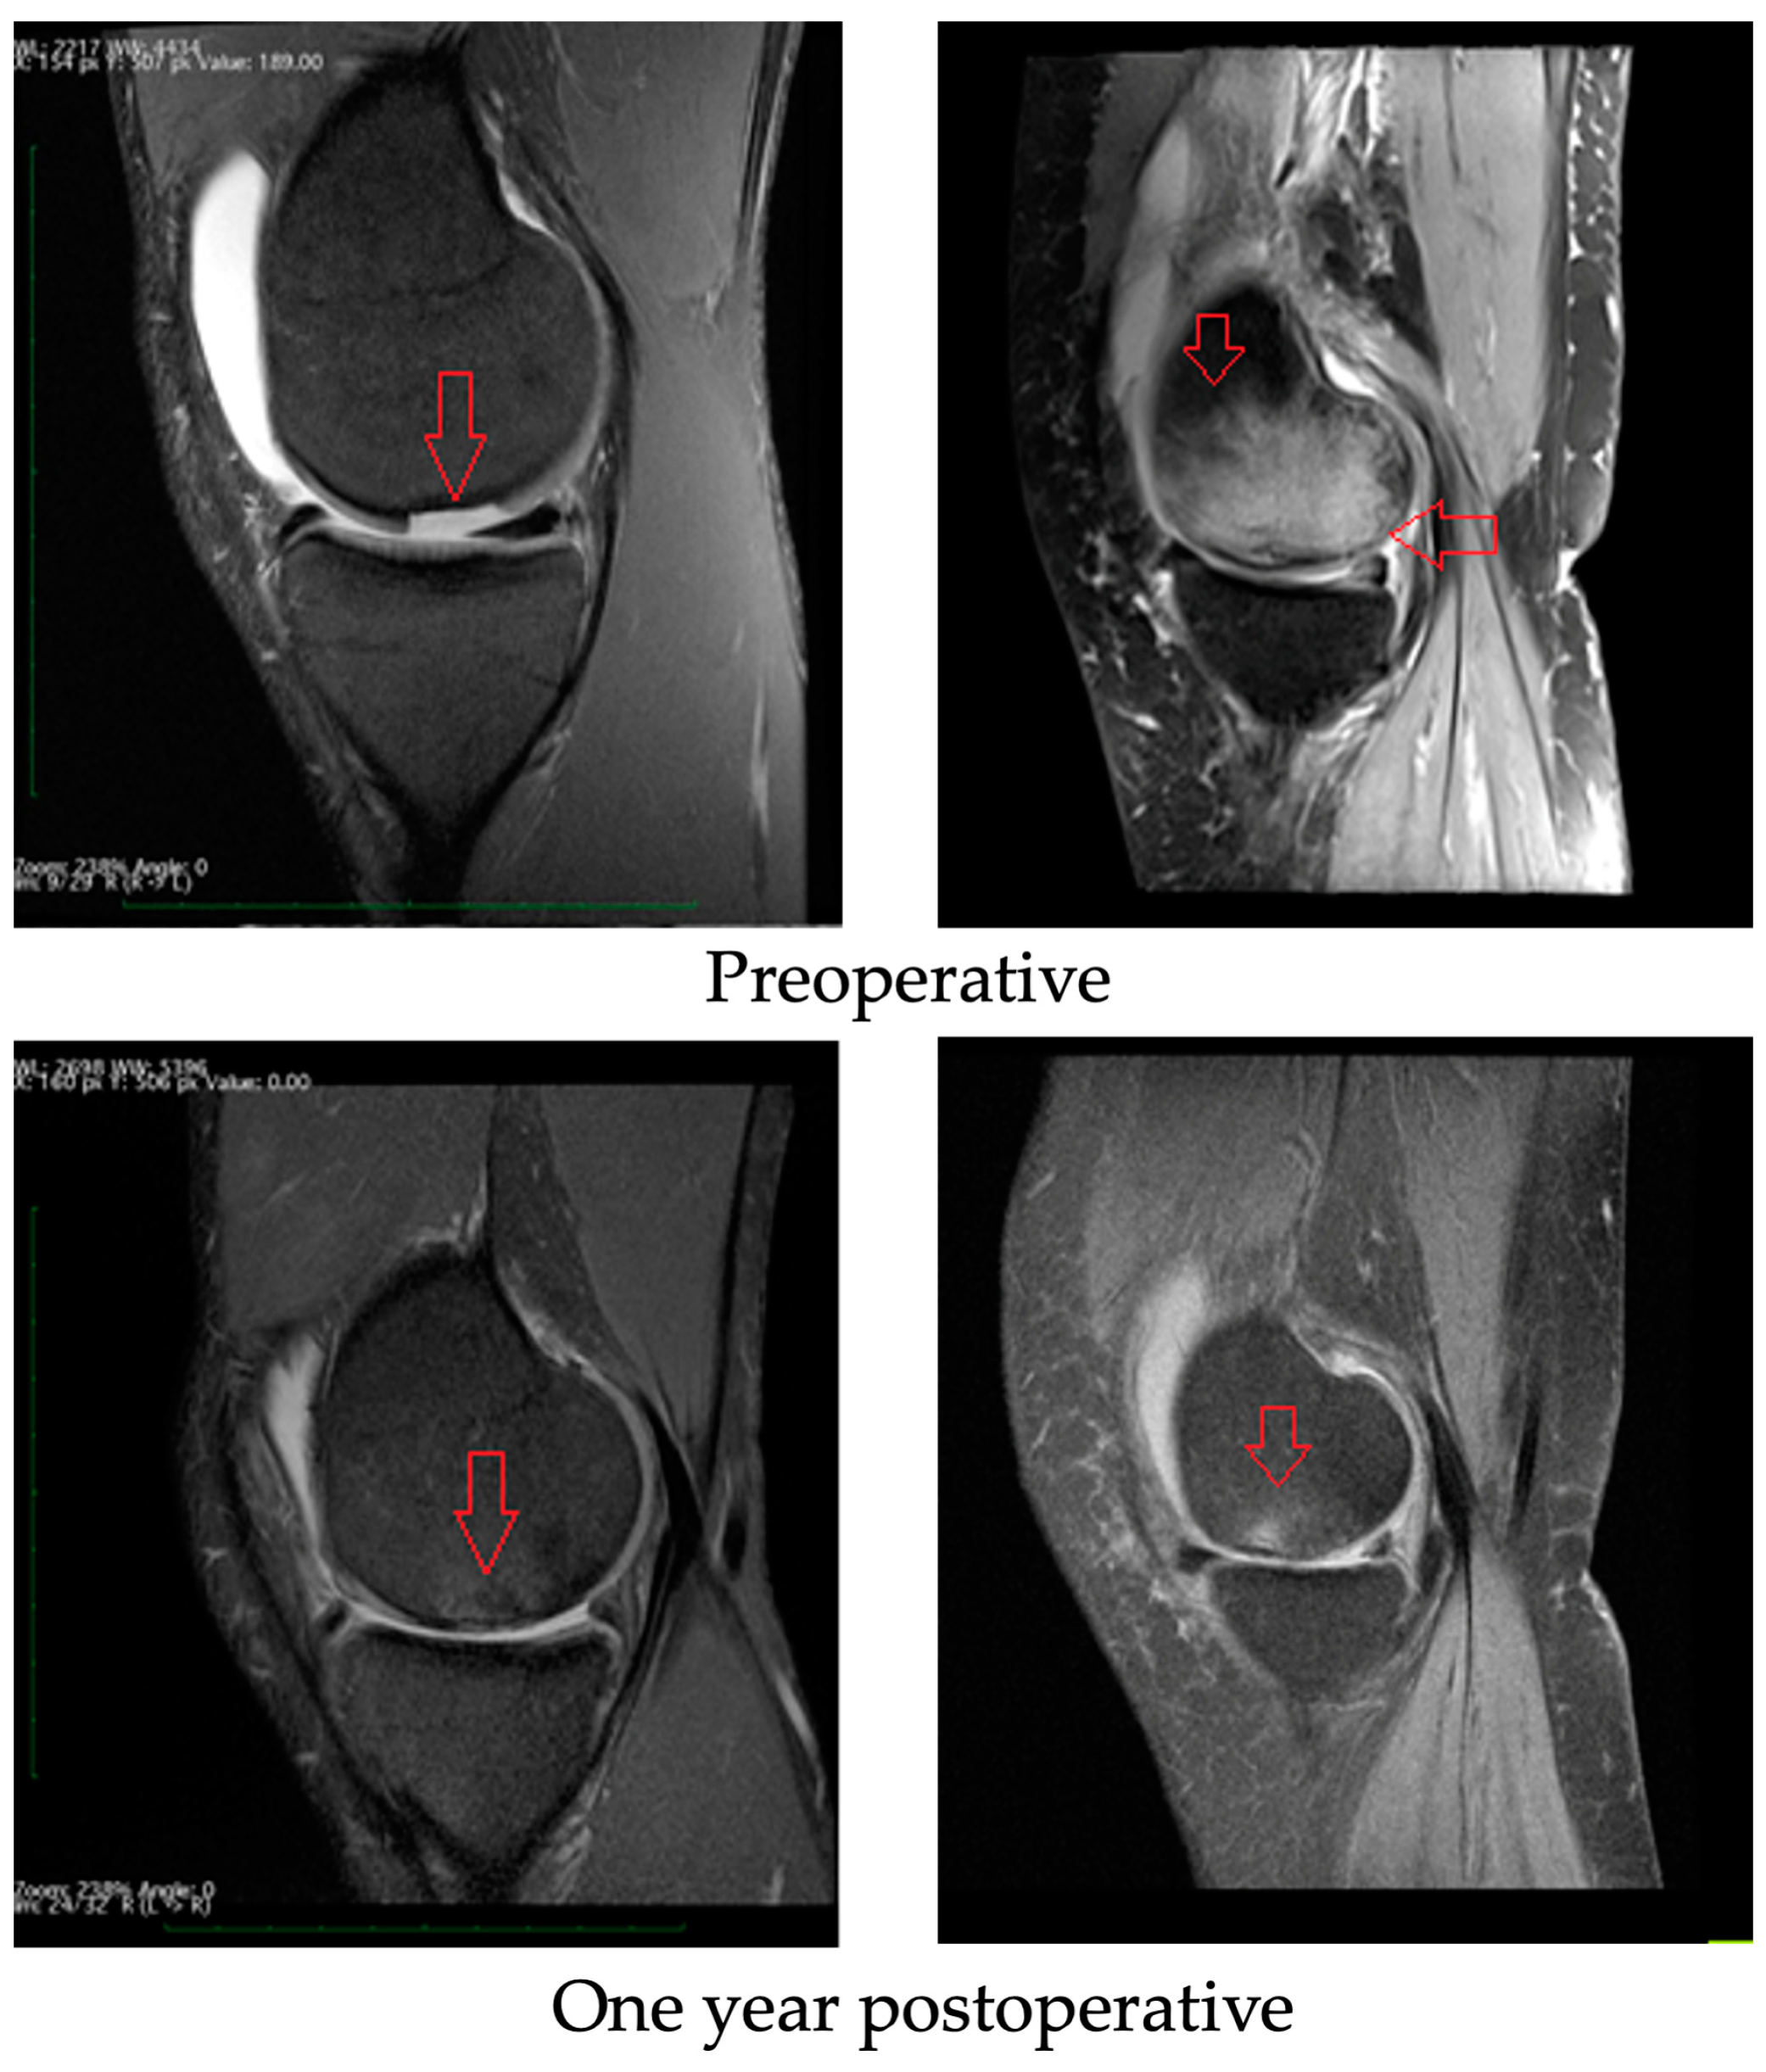

3.3. Radiological Evaluation